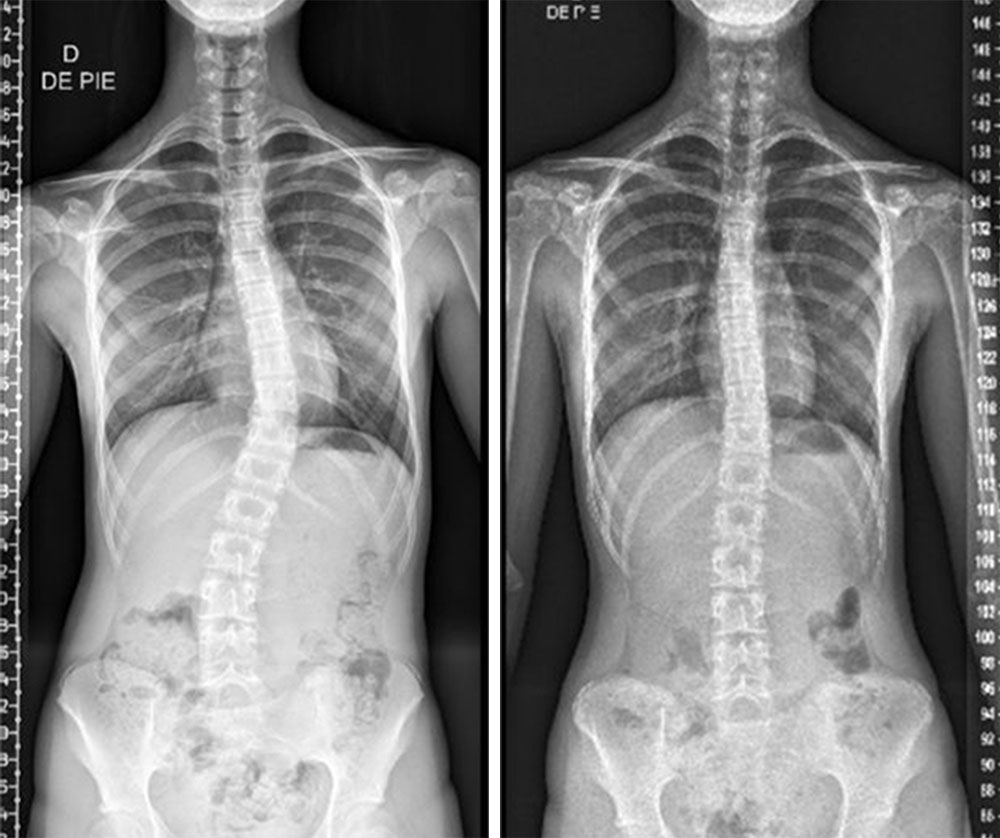

تقييم اعوجاج العمود الفقري بعد 6 أشهر بدون الحزام: أهم مؤشر لتحديد نجاح العلاج…

تقييم اعوجاج العمود الفقري بعد 6 أشهر بدون الحزام: أهم مؤشر لتحديد نجاح العلاج يُعد اعوجاج العمود الفقري لدى المراهقين من أكثر الحالات التي تُقلق الأهل، خاصة عند بدء العلاج بالحزام الطبي (الدعامة). وغالبًا